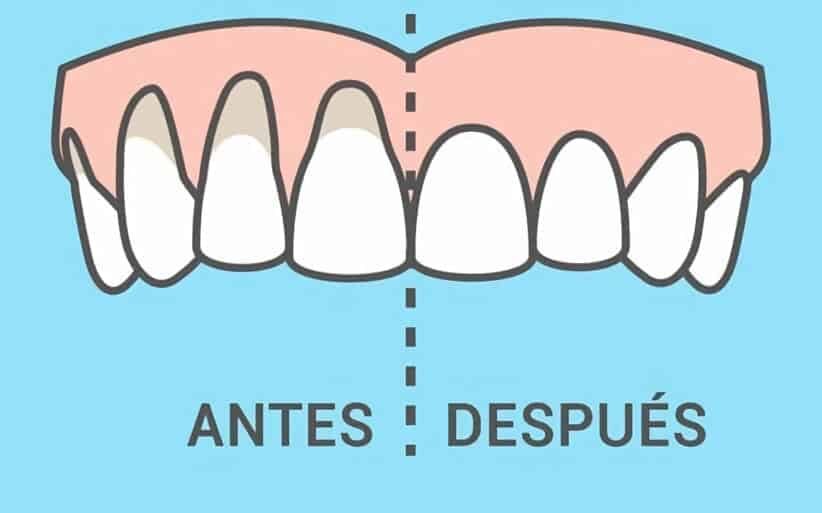

Soluciones al problema de encías retraídas

Lo cierto es que las encías no se regeneran por sí mismas, por lo que para curar encías retraídas es necesario acudir a un periodoncista.

Lo primero y más importante, antes de realizar algún tipo de tratamiento para las encías retraídas de tipo quirúrgico, es eliminar la causa que ha producido la encía retraída.

Colgajo movilizado coronalmente (estiramiento de encías)

En los pacientes que tienen conservadas las papilas interdentarias (el “triangulito” de encía que hay entre diente y diente), se puede llevar a cabo una técnica de estiramiento de encía.

Si la encía lo permite, se realiza un estiramiento de la misma para cubrir la raíz del diente.

Gracias a este método, la pieza dental y las encías recuperan su apariencia habitual sin la necesidad de recurrir a un injerto.

Microinjertos de encía

Combinada con la técnica anterior, se toma tejido del paladar mediante una mínima incisión y se cubre la encía.

Tradicionalmente, era necesario realizar una cirugía de mayor extensión, pero las nuevas técnicas permiten un injerto de encía, una cirugía poco invasiva, para la que solo es necesario dar 2 o 3 puntos de sutura en el paladar.